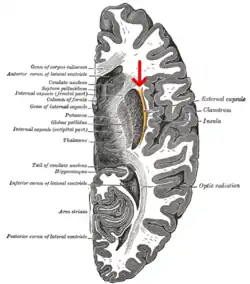

Die Capsula externa (deutsch: äußere Kapsel) ist eine relativ kleine Ansammlung von Nervenfasern im Gehirn. Anatomisch liegt sie medial des Claustrums und trennt dieses vom Putamen. Im weiteren Verlauf mündet sie um den Linsenkern in die Capsula interna ein.